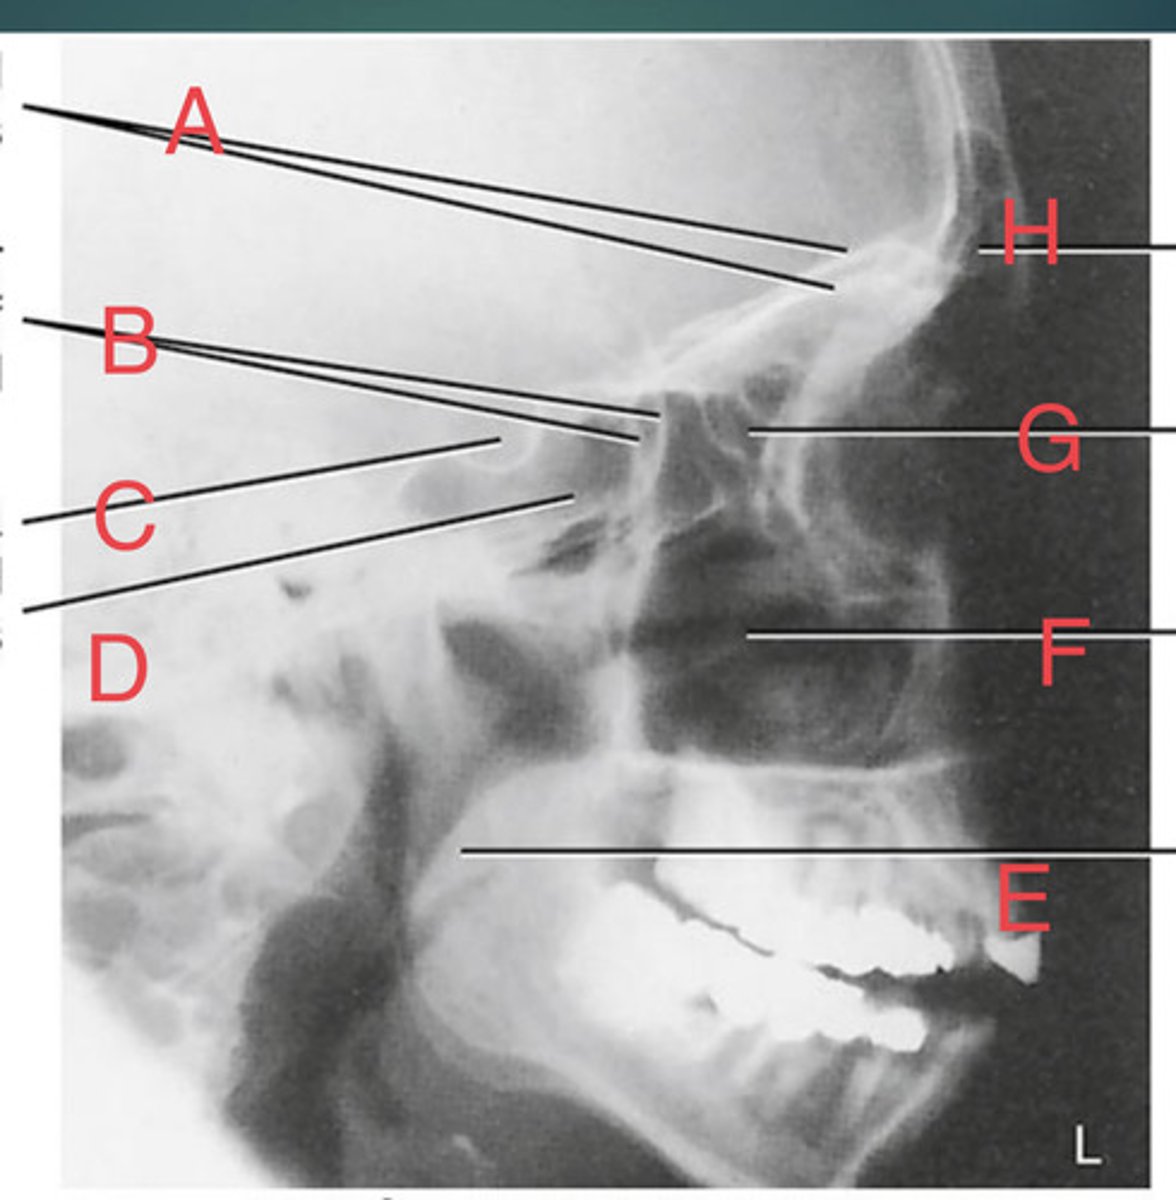

Lateral sinus

What position?

L. Orbital roofs

A.

L. Greater wings of sphenoid

B.

sella turcica of sphenoid

C.

L. Sphenoid sinus

D.

L. Rami of mandible

E.

L. Maxillary sinuses

F.

L. Ethmoid sinuses

G.

L. Frontal sinuses of frontal bone

H.